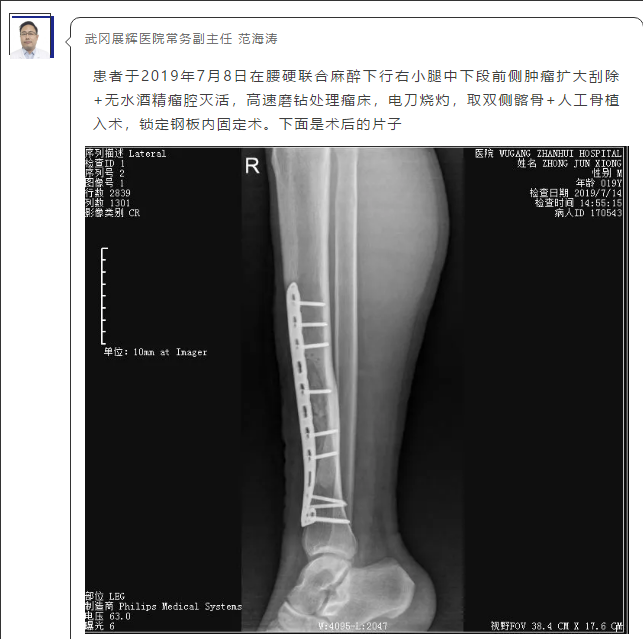

骨卫士特聘专家、武冈展辉医院常务副主任范海涛主任分享了“左侧胫骨病变”病例:

患者信息:男 19岁

主 诉:发现右小腿前侧肿物一年。

现 病 史:患者诉于2018年5月撞伤右小腿后局部肿胀,无明显疼痛,肿胀无消退,且进行性加重。无畏寒,发热,盗汗等不适。当时未予重视,未行特殊检查。后肿胀无消退,在某医院就诊,完善X线:右胫骨远端骨质破坏。

查 体:右小腿前侧肿胀,局部皮下无明显肿胀 色素沉着,无静脉曲张,局部皮温不高,有压痛,可触及10X3X2cm包块边界清质硬,固定。

影像表现:相关片子如下,点击可查看大图。